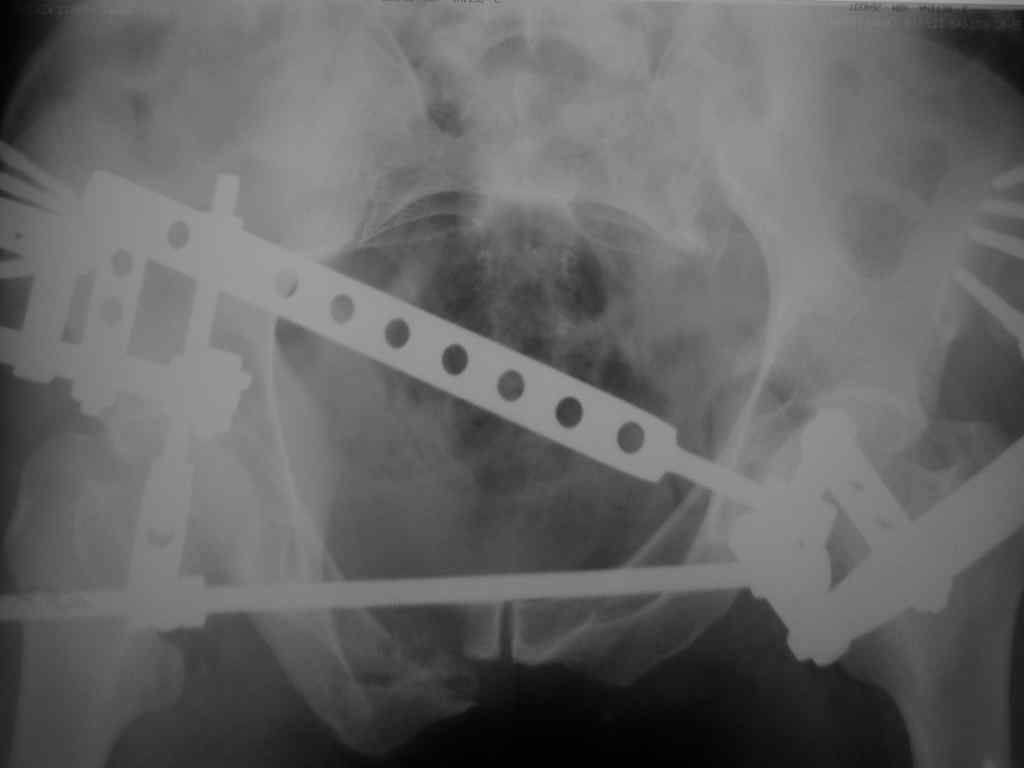

Владимир Бахарев 17 Ноябрь 2006, 13:30

Еще снимок